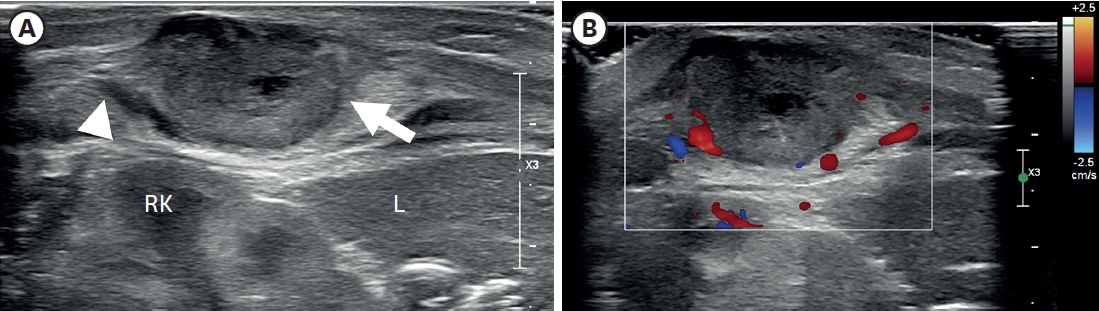

Fig. 1.

Ultrasonography of the right flank palpable lesion. (A) A lobulated soft tissue lesion (arrow) and is connected with (arrowhead) the muscular layer of the body wall, just outside of the RK and L, with an internal necrotic hypoechoic portion. (B) Doppler study shows increased vascularity in the mass lesion’s peripheral portion and surrounding areas.

RK, right kidney; L, liver.

A 3.3 kg female baby was born at 39 weeks gestation with a mass on the right chest wall, and she was admitted to the hospital. Except for the mass, the patient was healthy and had no comorbid diseases such as congenital anomalies. The mass was approximately 3 cm long, hard, fixed, and well defined, with no symptoms such as pain or skin changes. The ultrasound (US) examination (

Fig. 1) showed a lobulated soft tissue lesion in the muscular layer, with an internal necrotic hypoechoic portion. Magnetic resonance imaging (MRI,